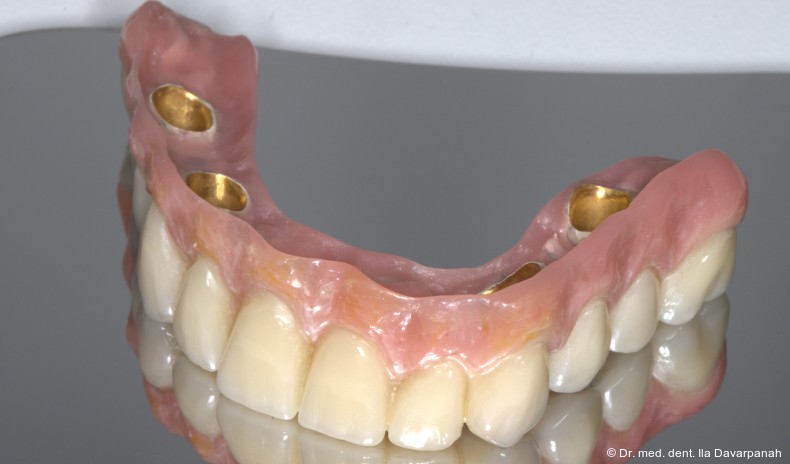

Auf Basis des digitalen Mock-ups wurden die Zirkonoxid-Primärkappen, galvanisch hergestellten Sekundärkappen sowie das NEM-Tertiärgerüst laborseitig gefertigt (Abb. 13+14). Die intraorale Verklebung der Sekundärkappen mit dem Tertiärgerüst erfolgte spannungsfrei im Mund (Abb. 15–17).

Eingliederung der Reise- und Definitivprothese

Nach Verkleben der sekundären Galvanokappen mit dem Tertiärgerüst verbleiben die Primärzirkonkappen im Mund. Um dem Patienten auf Basis dieser Pfeiler eine Interimsversorgung geben zu können, wird eine sogenannte Reiseprothese mit der Ästhetik und Funktion der finalen Versorgung hergestellt, welche auch als Referenz hierfür dient (Abb. 18+19).